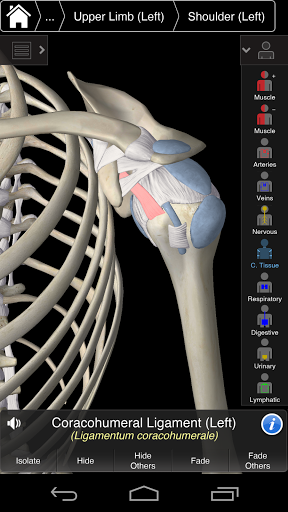

Основна анатомія 3 - це найновіша технологія та новаторський дизайн. Ріжучий 3D-графічний движок, зроблений на замовлення 3D4Medical з усього світу, наділений високоінформативною анатомічною моделлю і забезпечує високу якість графіки, яку не може досягти ніхто інший конкурент.

Програма являє собою унікальний підхід до вивчення загальної анатомії. Графіка не має аналогів і навчається, використовуючи інформативний контент та інноваційні функції, багатий та захоплюючий досвід.

Основна Анатомія 3 чутлива, візуально приголомшлива і легка. Додаток повністю 3D, що означає, що ви можете переглядати будь-яку анатомічну структуру окремо, а також з будь-якого кута.

Основна Анатомія 3 розроблена з урахуванням користувача - сам орган стає інтерфейсом. На відміну від інших 3D-додатків, які покладаються на попередньо визначені анатомічні механізми та регіональні розділи для керівництва користувача, 3D4Medical's Essential Anatomy 3 дозволяє знайти те, що ви шукаєте, без ускладнень.

---- Більше 4000 дуже детальних анатомічних структур

---- Латинська номенклатура для кожної анатомічної структури